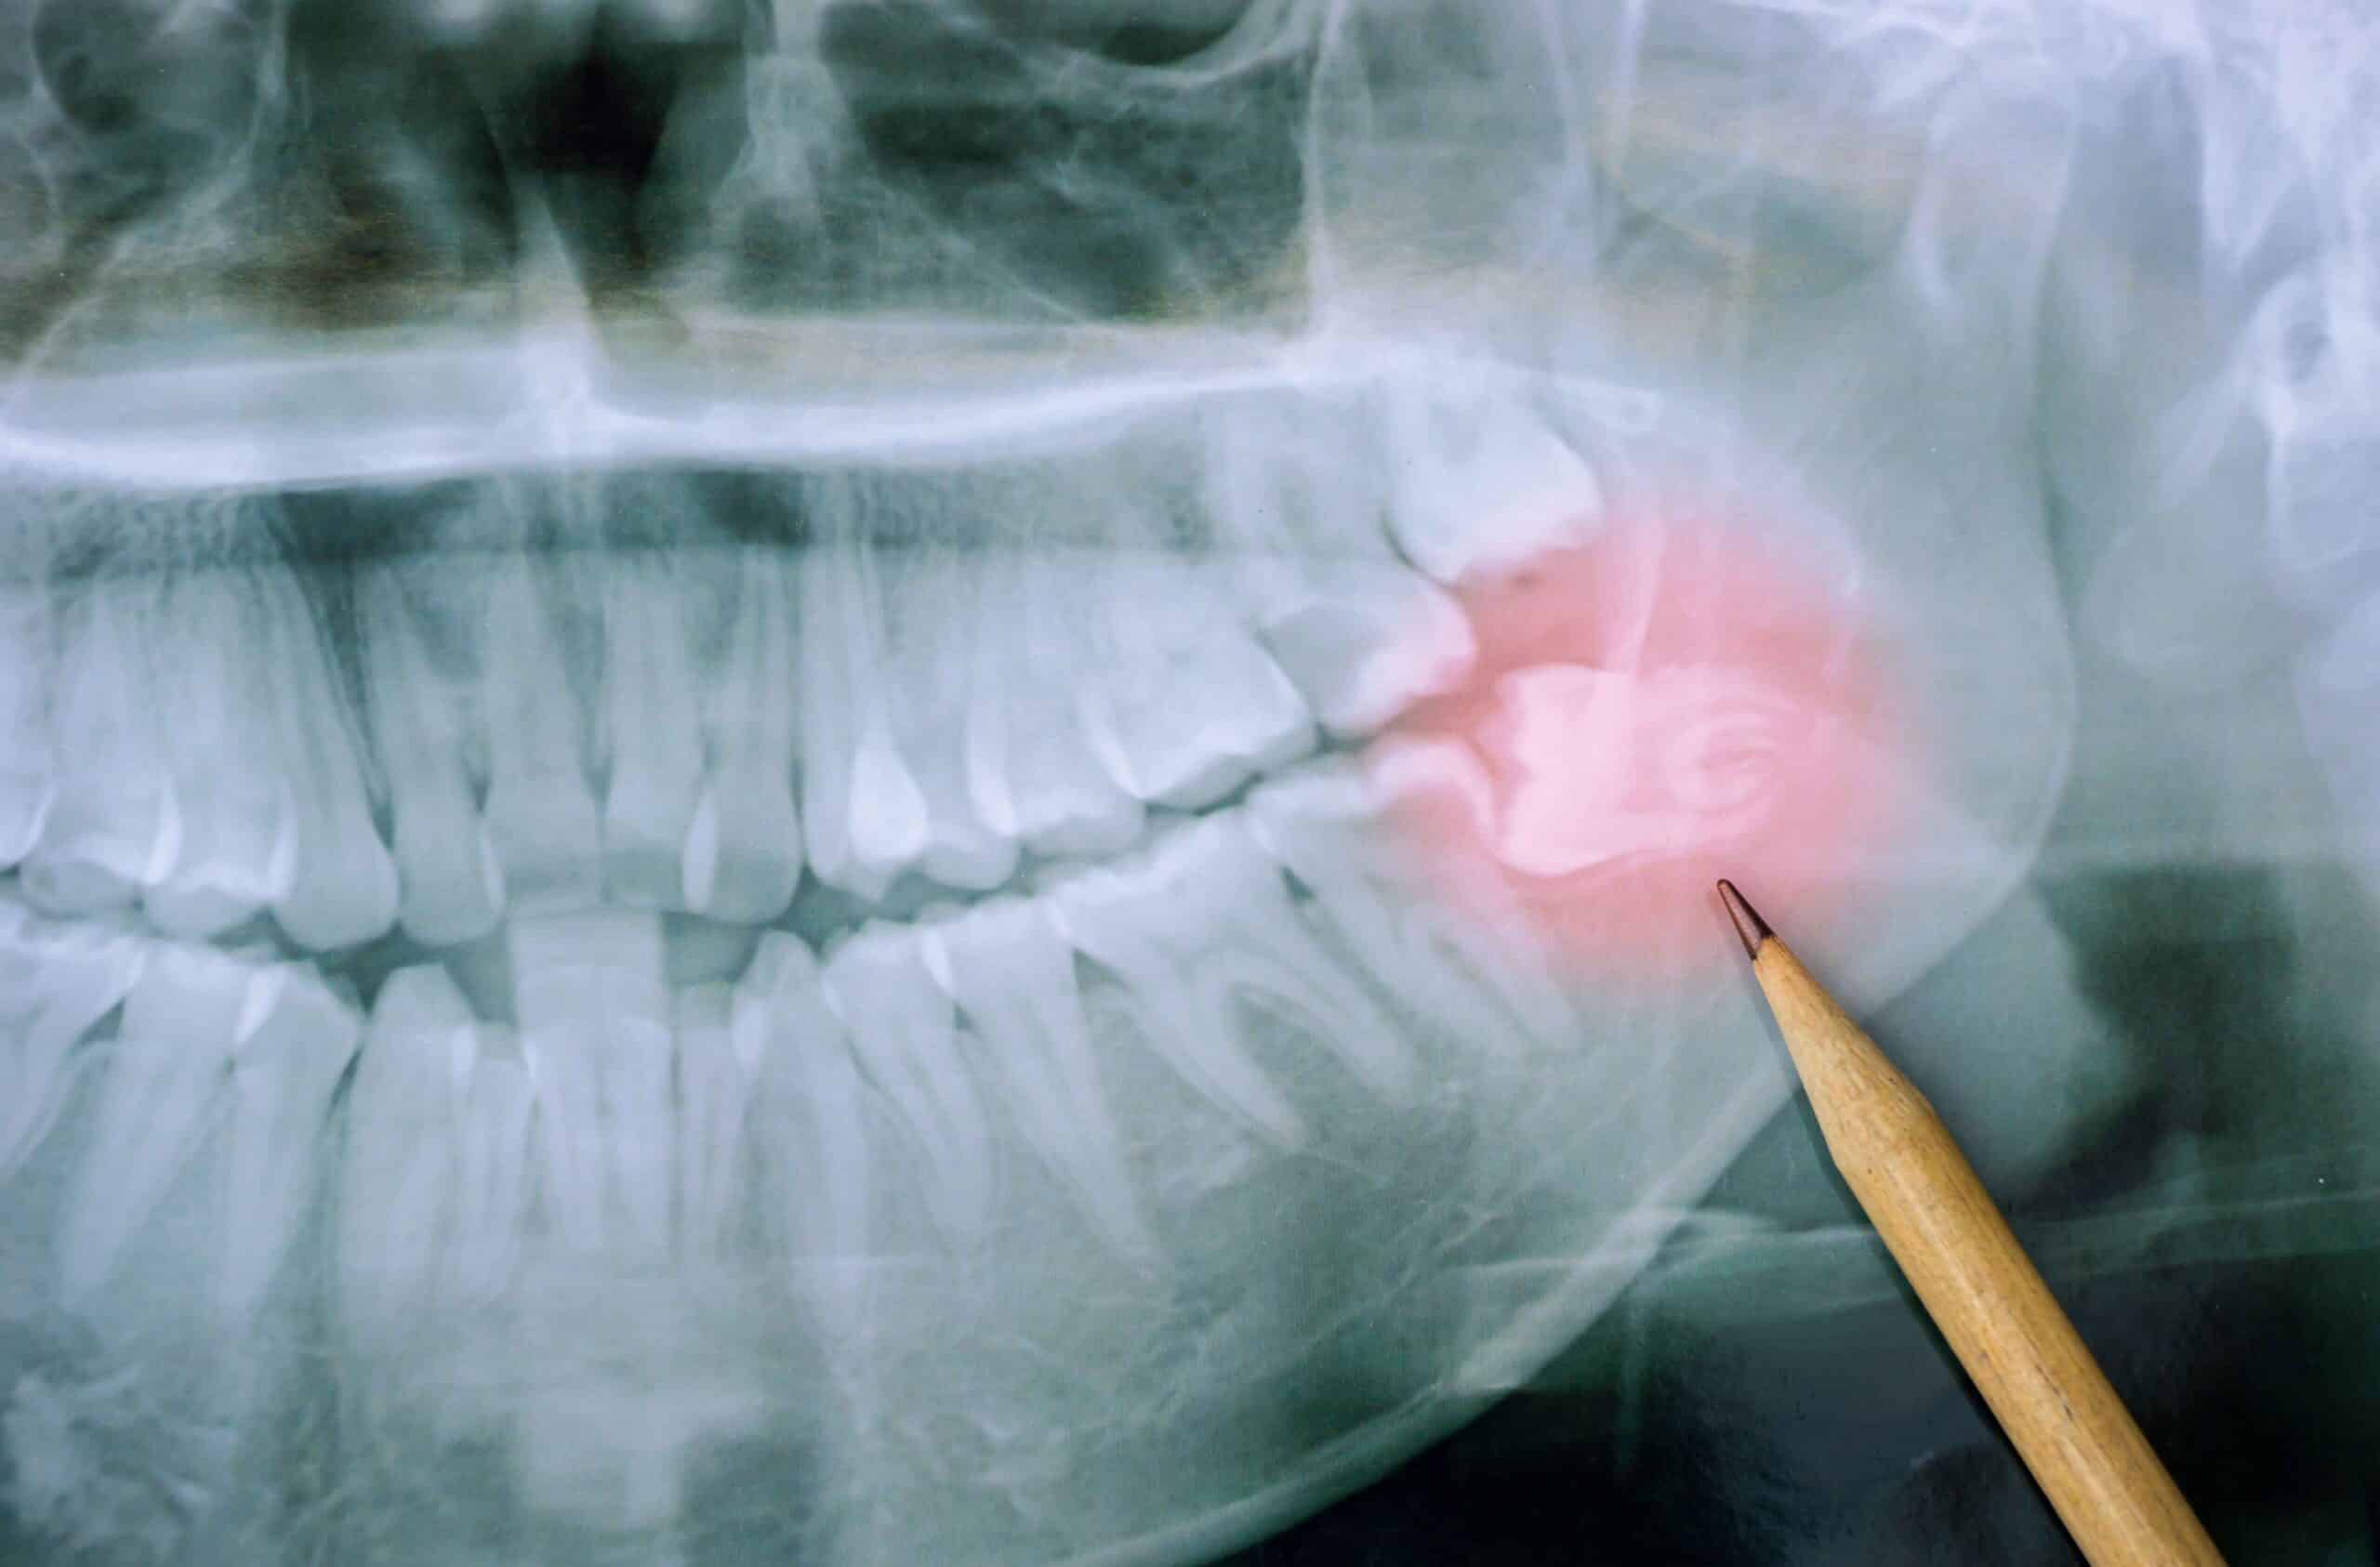

Welcome to our comprehensive guide on wisdom teeth, where we’ll dive into everything you need to know about these fascinating but sometimes troublesome molars. We’ve